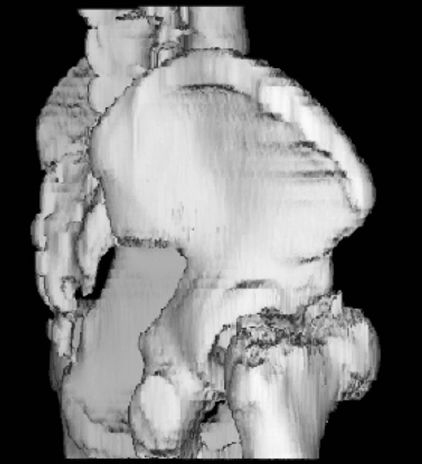

正常肩关节

肩胛骨骨折

分型–肩胛骨体部骨折

常见–肩胛颈部骨折–肩胛盂骨折–喙突骨折–肩峰骨折,移位多不明显。

肩锁关节脱位

肱骨外科颈骨折